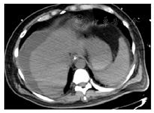

2021年10月28日于青岛大学附属医院行腹部CT(图1)提示肝硬化、脾大、门脉高压、腹水表现、胆囊区高密度影。2021年10月28日胸部CT(图2)提示左肺上叶炎性结节可能,双肺坠积性炎症可能性大,双侧胸膜增厚,右侧少量胸腔积液、心腔密度减低。